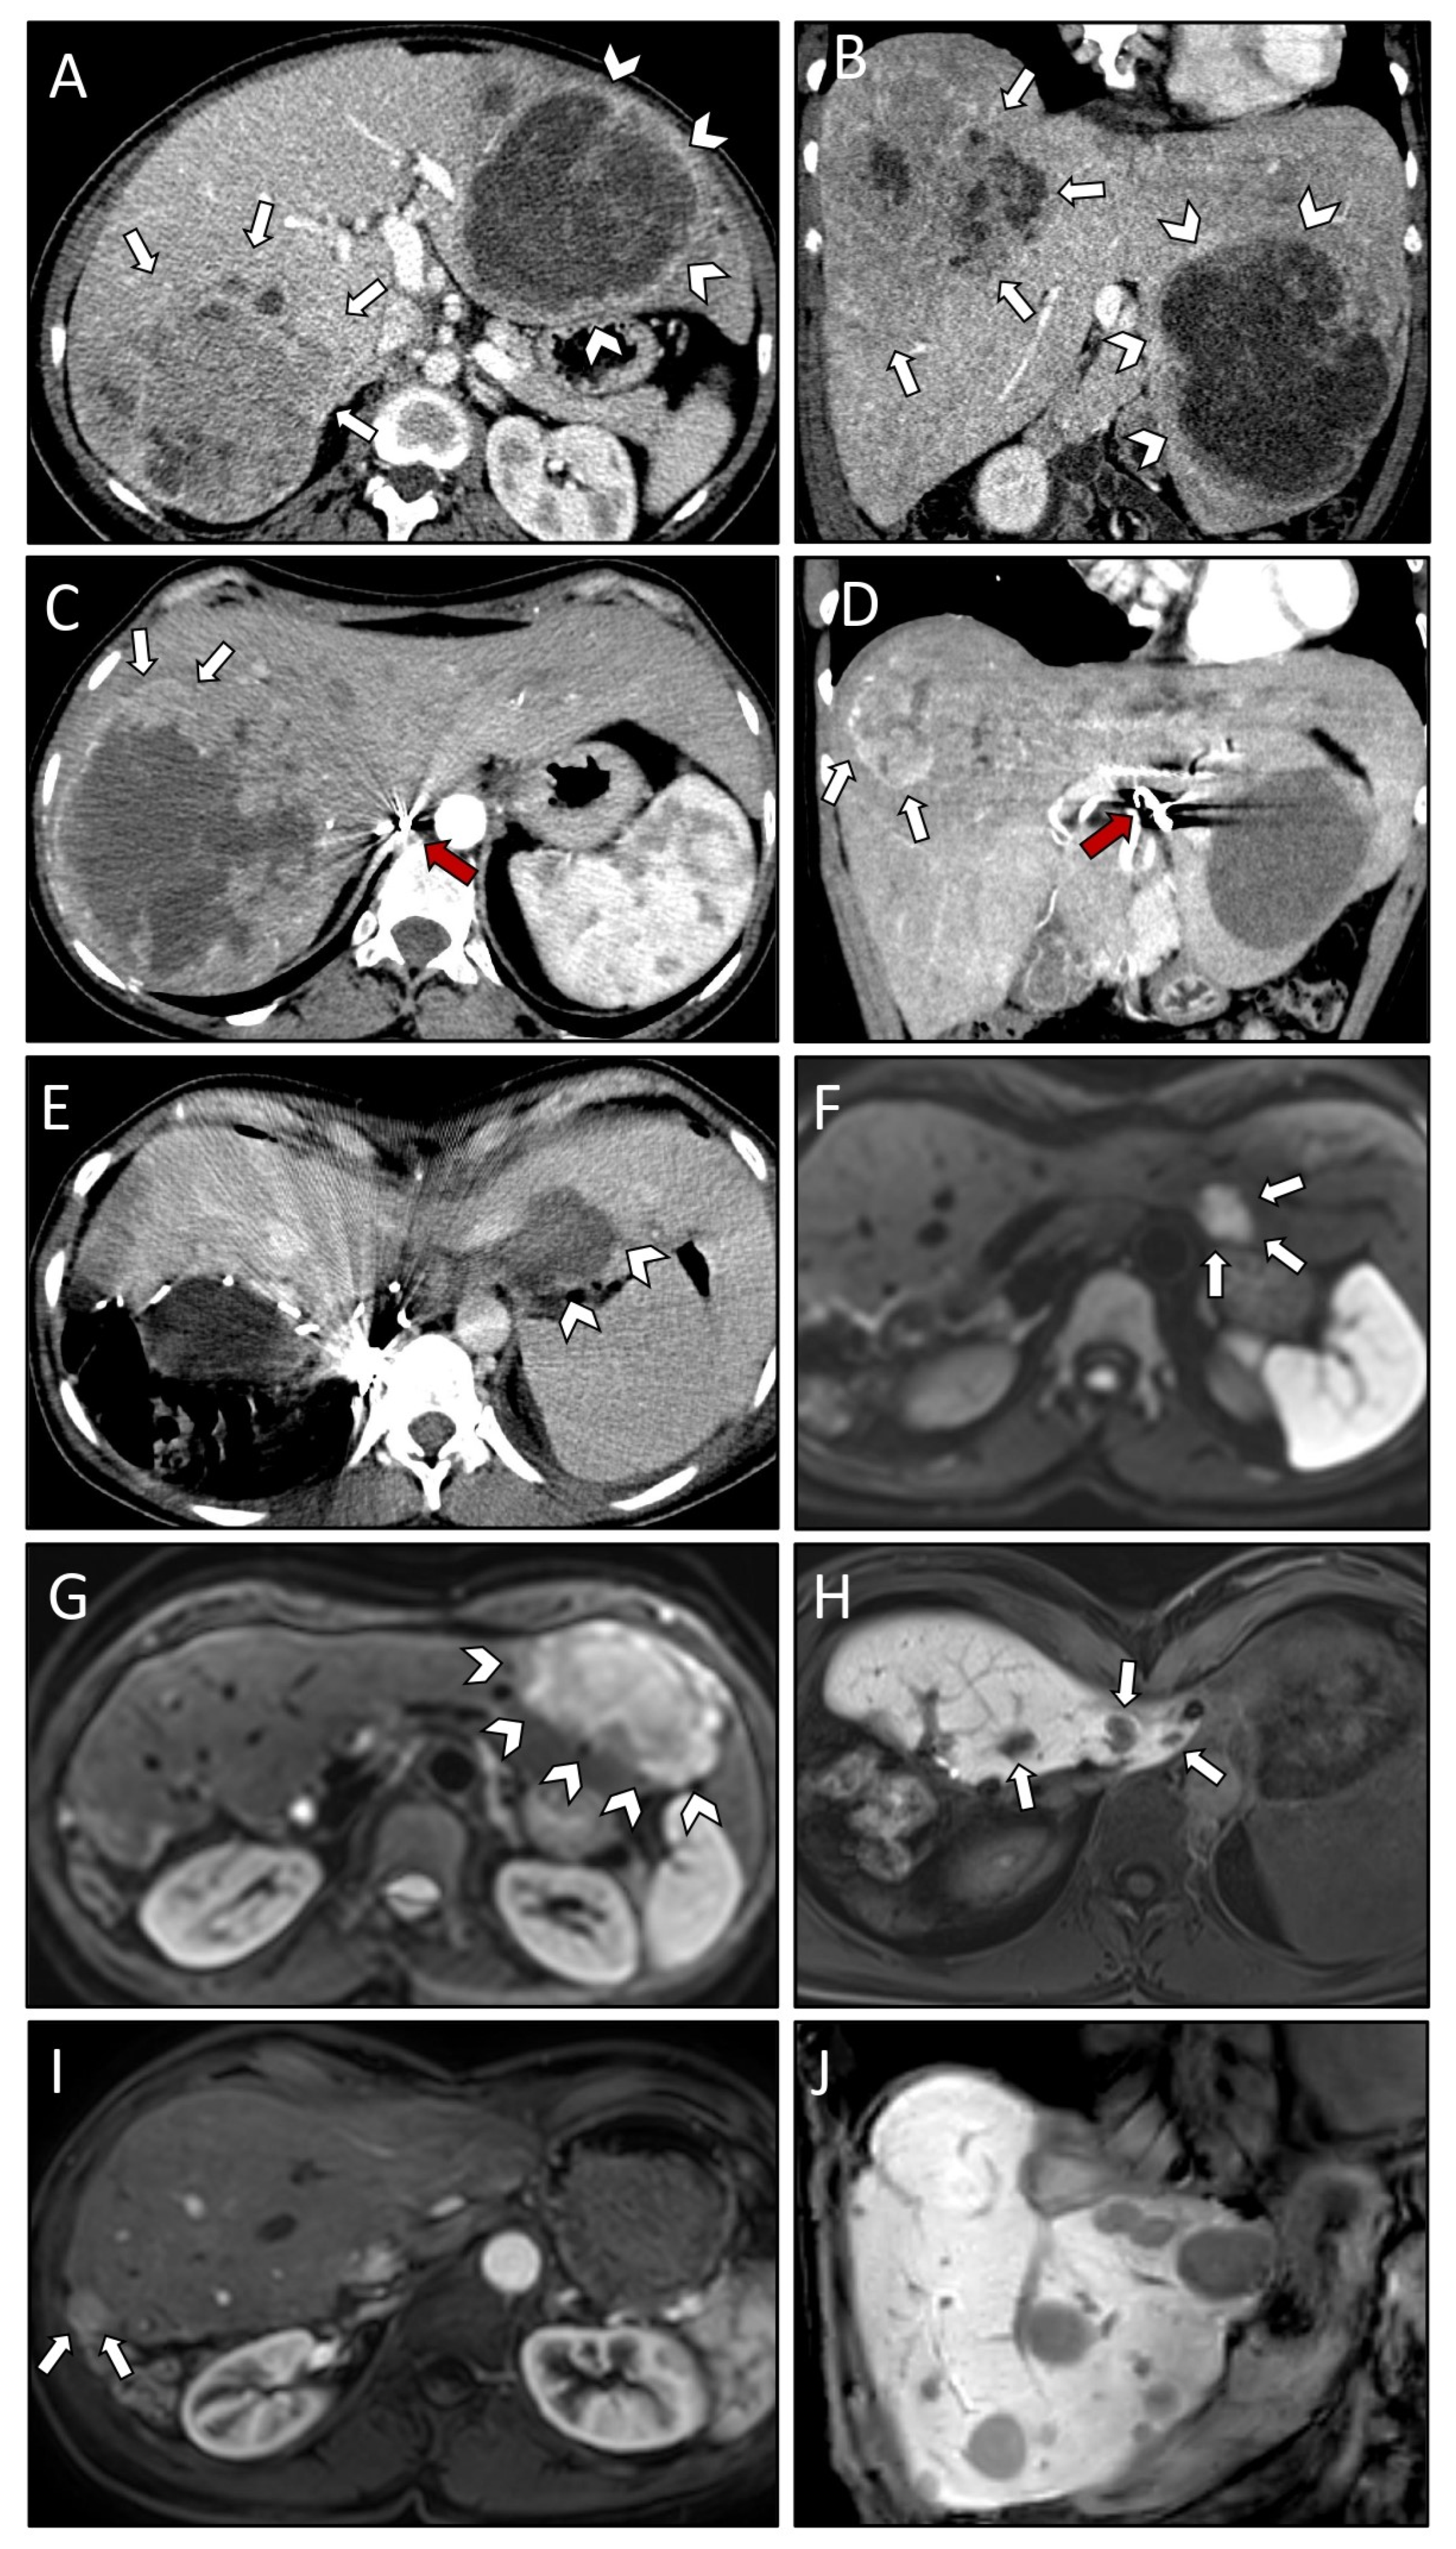

| Case #3 | Treatment | Comments | Liver Segments | Classification | Complications |

| 05.05.2014 | TAE | Contour™ PVA Embolization Particles (255–500 μm), Pushable Fibered Microcoils (Cook Medical), Soft Embolization Coils (Boston Scientific), MicroPlex® Coil System (MicroVention, Inc.) | IVa, IVb, V, VI, VII | Initial | Postembolization syndrome (CD I) |

| 24.06.2014 | TAE | Contour™ PVA Embolization Particles (150–500 μm) | II, III | Initial | Postembolization syndrome (CD I) |

| 22.07.2014 | TAE | Contour™ PVA Embolization Particles (250–350 μm) | IVa, IVb, V, VI, VII | Initial | none |

| 10.11.2014 | TAE | Embozene™ Microspheres (2 × 100 μm) | IVa, IVb, V, VI, VII | Initial | none |

| 08.04.2015 | TAE | Embozene™ Microspheres (1 × 100 μm, 1 × 250 μm, 1 × 400 μm, 1 × 500 μm) | II, III | Initial | none |

| 06.05.2015 | TAE | Embozene™ Microspheres (1 × 100 μm, 1 × 200 μm) | IVa, IVb, V, VI, VII | Initial | none |

| 26.08.2015 | Surgery | Resection of left lateral segments | II + III | Initial | Bilioma (CD I) |

| 08.07.2016 | TAE | Embozene™ Microspheres (2 × 100 μm, 1 × 250 μm) | IVa, IVb, V, VI, VII | Local recurrence | none |

| 21.11.2016 | SRFA | 3 lesions, 5.1 cm max. diameter, 8 needles, 63 min ablation time | IVa, VII, VIII | Local recurrence | none |

| 07.12.2016 | SRFA | 2 lesions, 2.3 cm max. diameter, 4 needles, 59 min ablation time | IVa, VIII; | Local recurrence, new lesion | none |

| 26.01.2017 | SRFA | 2 lesions, 8 cm max. diameter, 9 needles, 74 min ablation time | VI | Local recurrence | Right pleural effusion, pigtail catheter (CD IIIa) |

| 23.03.2017 | SRFA | 2 lesions, 8 cm max. diameter, 20 needles, 104 min ablation time | V, VI | Local recurrence | none |

| 30.10.2017 | SRFA | 8 lesions, 2 cm max. diameter, 9 needles, 32 min ablation time | V, VI | Local recurrence, new lesion | none |

| 04.04.2018 | SRFA | 4 lesions, 2 cm max. diameter, 10 needles, 36 min ablation time | V, VI, VII, VIII | Local recurrence, new lesion | none |

| 05.19–08.19 | Systemic therapy | Pazopanib | Distant recurrence | Leukocytopenia, Infection, Sepsis CTCAE III |